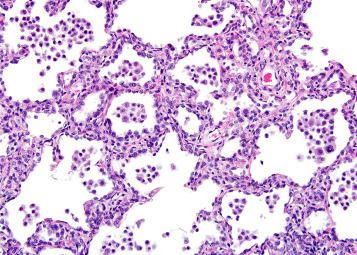

The lung is the most common site of metastasis of neoplasms in rats due to its extensive supply of small caliber blood vessels and lymphatics. Metastatic neoplasms are mostly epithelial and tend to be multiple. Common primary sites of origin of neoplasms metastatic to the lungs of rats include the skin, bone, mammary gland, Zymbal’s and harderian gland, and liver. Metastatic neoplastic cell emboli are often observed in pulmonary blood vessels and lymphatics. Intrapulmonary metastasis is often seen with chemically induced alveolar/bronchiolar carcinomas and occurs via the lymphatics. Extrapulmonary metastases of alveolar/bronchiolar carcinoma have been identified in the mediastinum. Systemic hematopoietic/lymphoid neoplasms such as mononuclear cell leukemia and histiocytic sarcoma are common in the lungs of aged rats. These neoplasms arise within the spleen and other lymphoid organs, and tend to be diffuse within the lung and may resemble inflammatory lesions. The circulating neoplastic cells are observed in the pulmonary capillaries and cause increased cellularity (Figure 23.52 ). In addition to the increased cellularity, hemorrhage and thrombosis may be associated with the infiltrating cells.

Figure 23.52.

Mononuclear cell leukemia in the rat lung. Note lymphocytes within blood vessels and capillaries.